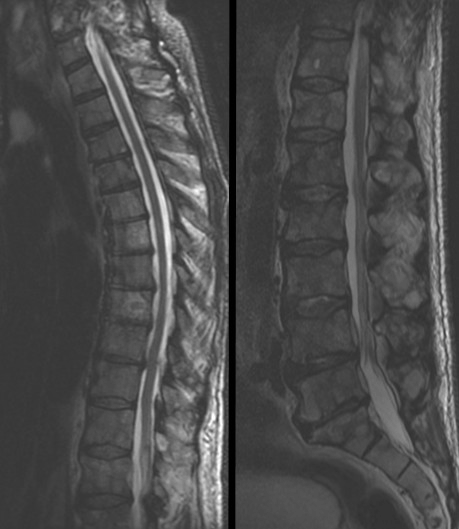

Computed tomography (CT) imaging of abdomen, pelvis and thorax showed diffuse osteolytic metastases involving the entire spine, ribs and pelvis, and there was an isolated expansile lytic lesion in the left iliac bone (Figures 1, 2). Magnetic resonance imaging (MRI) study of the entire spine showed similar findings but did not show any evidence of fracture or dislocation or significant cord compression (Figure 3). Whole body Technetium bone scan showed diffuse reduce uptake (cold spots) involving several ribs and vertebrae suggestive of extensive osteolytic activity, along with mild irregular uptake suggestive of minimal osteoblastic component (Figure 4).

Figure 3: MRI scan of the entire spine without contrast shows vertebral bony lesions with no cord compression or fracture..

After one year of therapy, his PSA has normalized at 0.66 ng/mL and he was asymptomatic. Post-treatment CT scan of pelvis showed considerable regression of left iliac lytic bone lesion (Figure 5). MRI spine showed significant resolution of lytic lesions with mild residual lesions involving several ribs and vertebrae, and no new lesions were detected.